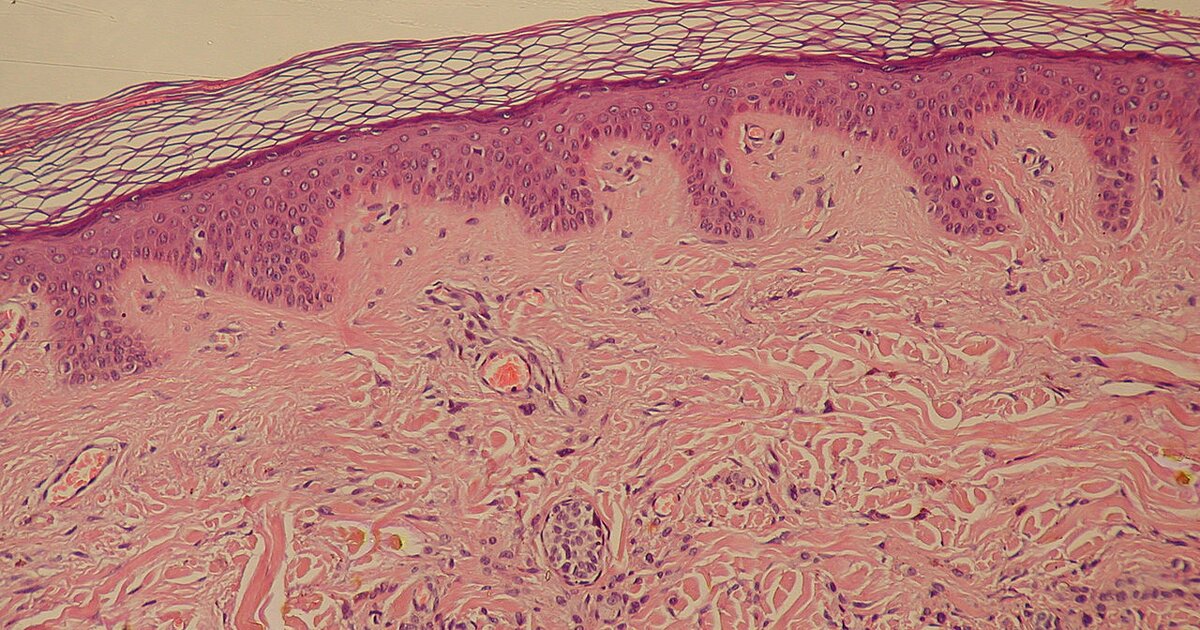

Эпидермис обнаружили у ребенка - фото презентация